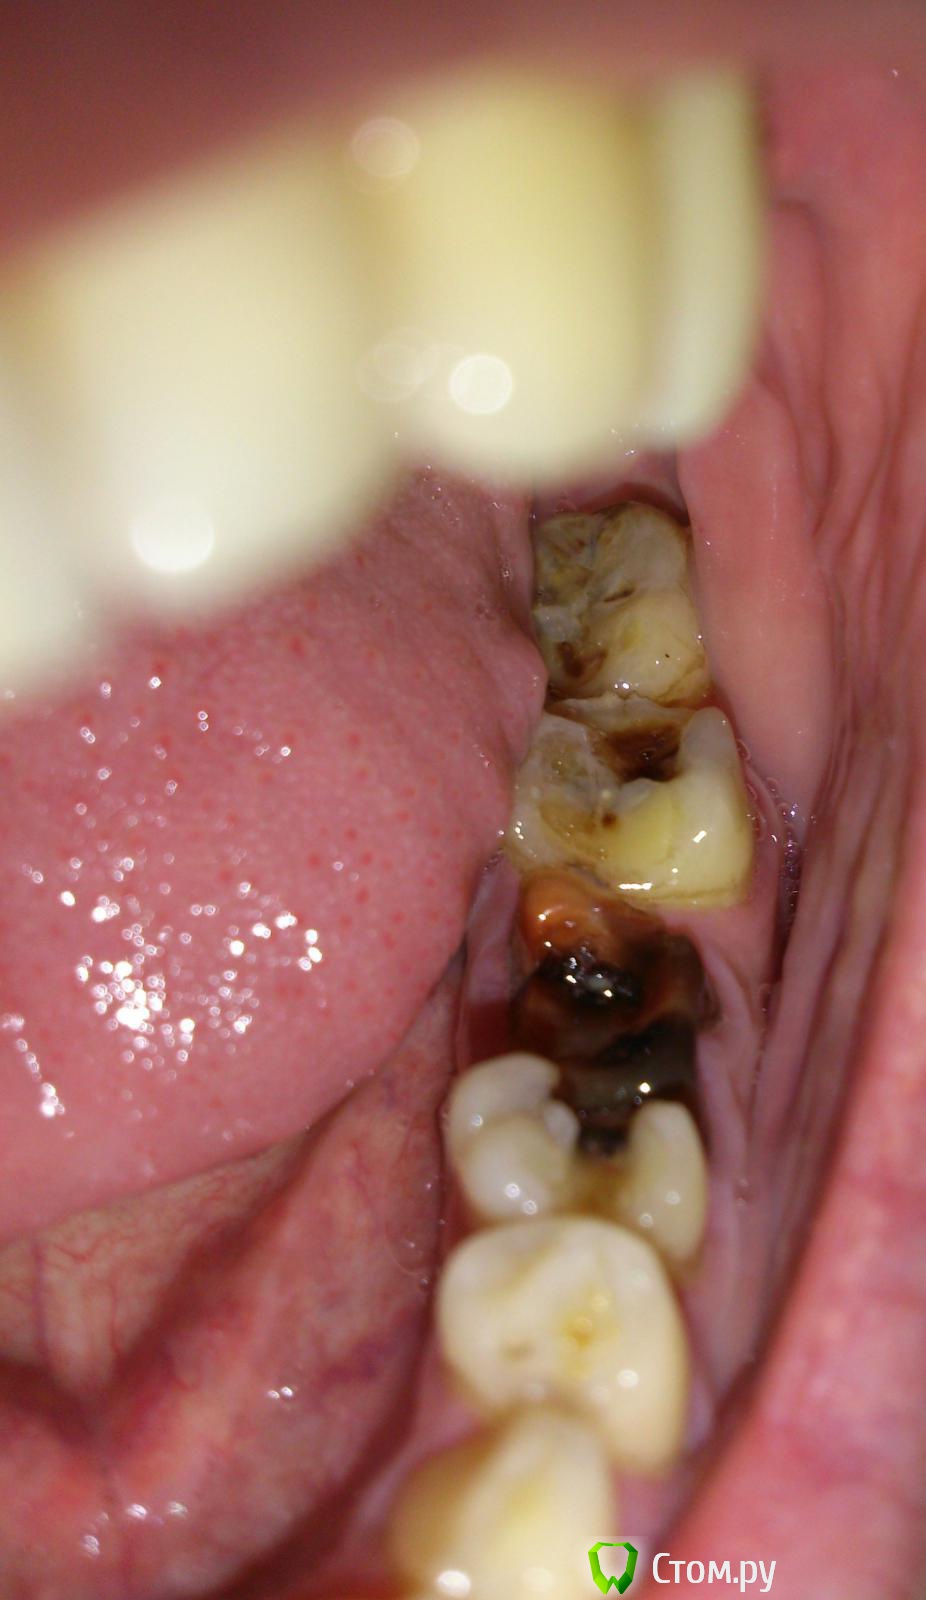

govorov Опубликовано 5 декабря, 2013 Поделиться Опубликовано 5 декабря, 2013 Подскажите, пожалуйста,что и в какой последовательности лучше делать с этими зубами?Зубы на фото в ссылке ниже. 6-й давно лечили, пломбировали. Несколько лет назад откололась примерно половина зуба с пломбой. Хотели вырвать, но не настаивали, я оставил. Через некоторое время потемнел, но особо не беспокоил. Сейчас, иногда, вечером или ночью болит. Днём нормально: не болит и есть на нём нормально. Соседние, вроде надо лечить? Нужно ли сначала удалять или что-то делать с этим 6-м? Если нужно удалять 6-й, можно ли сразу, вместо вырванного, вставить имплант, или вырвать, потом лечить остальные, потом делать имплант? Снимок корня 6-го _20131129_15633 - сделан 2013-11-29, _20121013_9451 - примерно год назад.Где это лучше делать (Долгопрудный, Москва)? И сколько это может стоить?Спасибо! Ссылка на комментарий

govorov Опубликовано 6 декабря, 2013 Автор Поделиться Опубликовано 6 декабря, 2013 Спасибо большое за ответы! Скажите ещё пожалуйста, какой главный аргумент за удаление 6-го? Не может ли быть так, что болят соседние, и достаточно их вылечить, а этот — 6-й — чёрный или красный, половина, но не болит ни кому не мешает? Ссылка на комментарий

IvanK Опубликовано 6 декабря, 2013 Поделиться Опубликовано 6 декабря, 2013 Спасибо большое за ответы! Скажите ещё пожалуйста, какой главный аргумент за удаление 6-го? Не может ли быть так, что болят соседние, и достаточно их вылечить, а этот — 6-й — чёрный или красный, половина, но не болит ни кому не мешает?соседние тоже могут болеть... причем большая их часть на фото... Ссылка на комментарий

govorov Опубликовано 6 декабря, 2013 Автор Поделиться Опубликовано 6 декабря, 2013 Так я предполагаю, что болят только соседние, а 6-й чёрный (или красный), но не болит, никому не мешает и как-то жуёт и, поэтому, удалять его НЕ нужно! Может такое быть?Чем плохи «корни отдельно друг от друга»? Они, наверно, несколько лет уже так (не меньше года). Там где делали снимки, сказали, что видели что-то плохое на корнях 6-го, типа, «кисту с гноем». Действительно там видно такое? Если видно, то лечится только удалением? Ссылка на комментарий